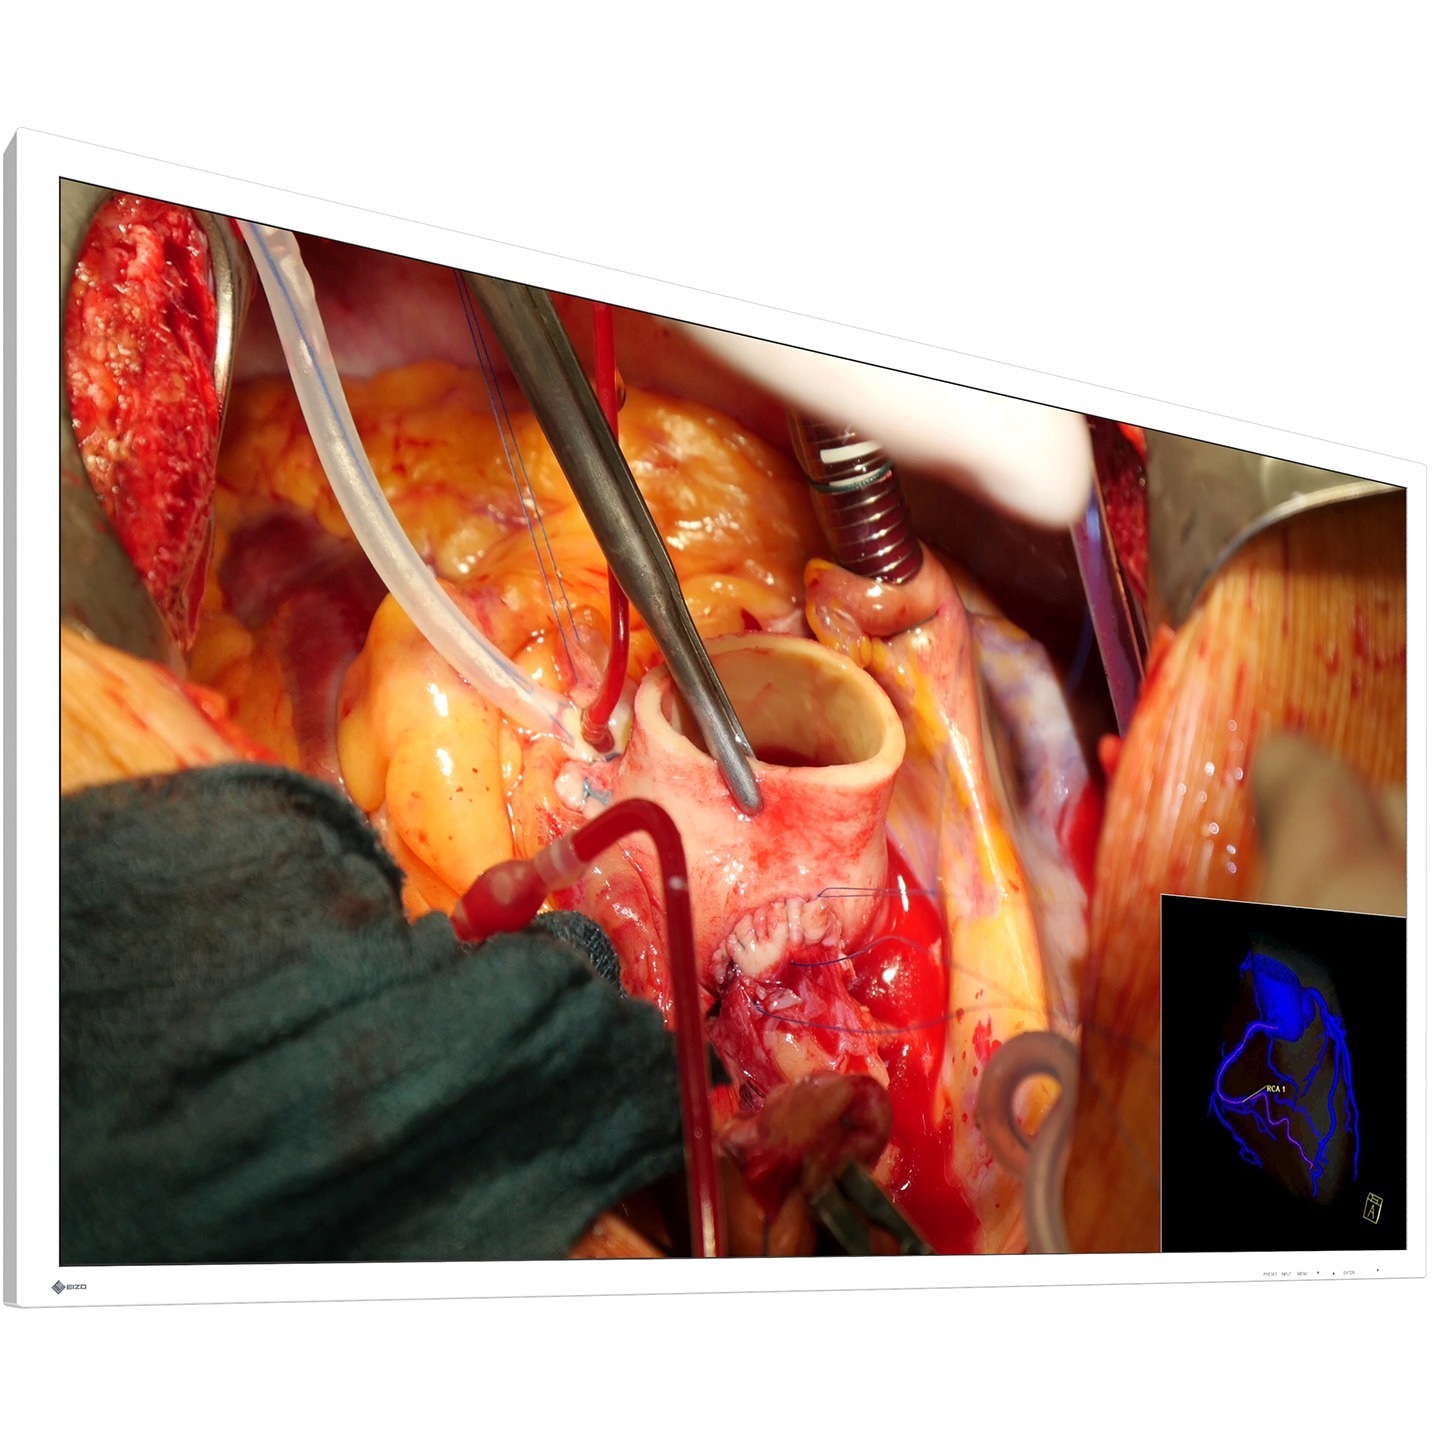

58-inch widescreen surgical monitor with 4K UHD display that faithfully reproduces surgical images.

This monitor uses an LCD panel with an energy-efficient LED backlight, a brightness of 300 cd/m² and a contrast ratio of 1000:1. It displays in 4K UHD resolution (3840 x 2160 pixels), and faithfully reproduces surgical images in high definition for endoscopy and microsurgery.

In single source mode, 4K images, as well as full HD images shot by conventional endoscopy and surgical cameras can be displayed in high definition without any delay, making full use of the monitor's 4K UHD resolution.

In dual source mode, two separate signal sources can be viewed simultaneously on one monitor screen side-by-side using the PaP (Picture-and-Picture) function. With the PiP (Picture-in-Picture) function a second signal can be displayed above the main signal. The size and position of the display window is adjustable when using PiP. In triple source mode, three signal sources can be displayed on the monitor screen, representing a third signal above two signals displayed side-by-side. This is useful when several images need to be viewed at once such as multiple modalities.

If multipe signal sources are simultaneously displayed on the monitor, each image's display mode (e.g. Gamma or DICOM) can be adjusted without affecting the presentation of the other image. This is perfect for multi-modality use, when endoscope, CT or MRI images are accurately displayed on the monitor.